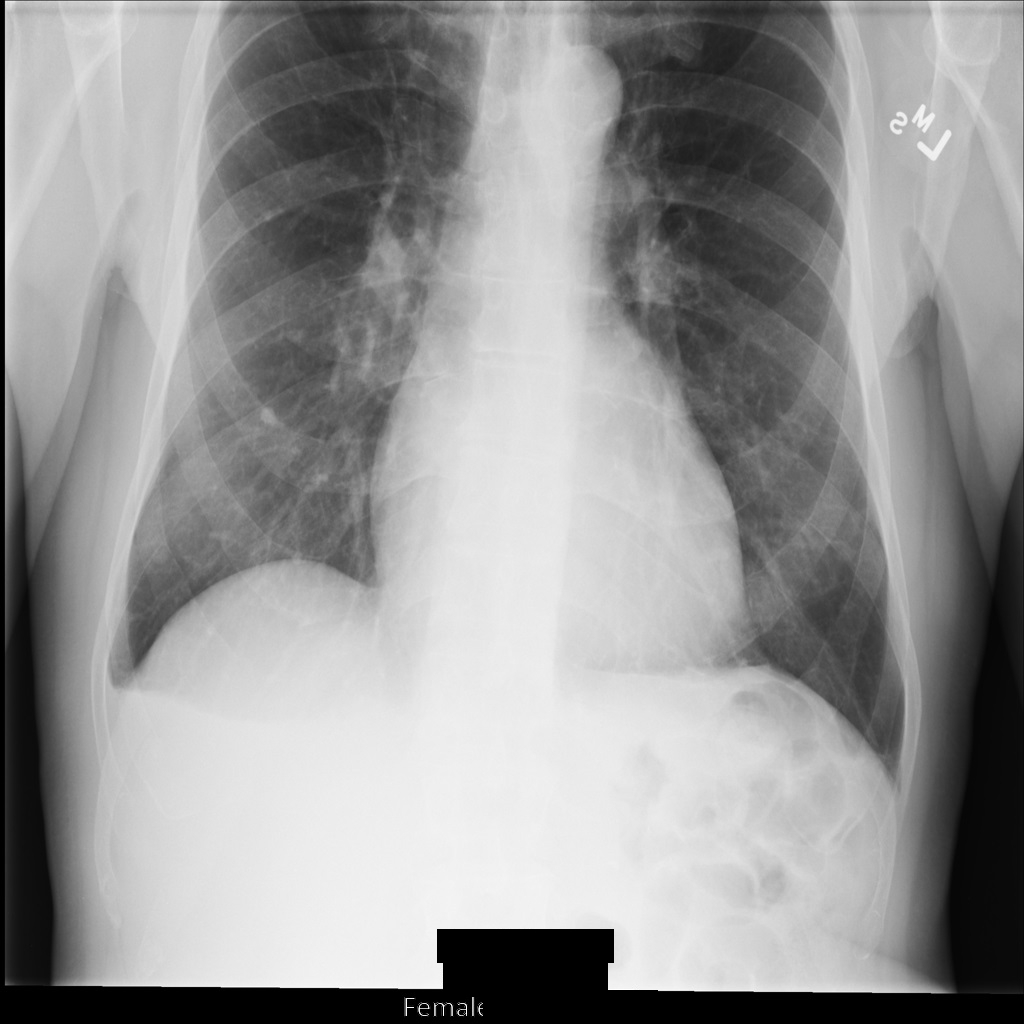

REDACT_SENSITIVE_TEXT_CLEAN_DESCRIPTORS を使用して画像を匿名化すると、画像は次のようになります。画像の下部にある焼き付きテキストの一部が秘匿化されていないことに注意してください。PatientSex (0010,0040) はデフォルトの DICOM infoType の 1 つではないため、テキスト Female は引き続き表示されます。

REDACT_SENSITIVE_TEXT_CLEAN_DESCRIPTORS を使用して匿名化された後の DICOM インスタンス。DICOM タグを匿名化する